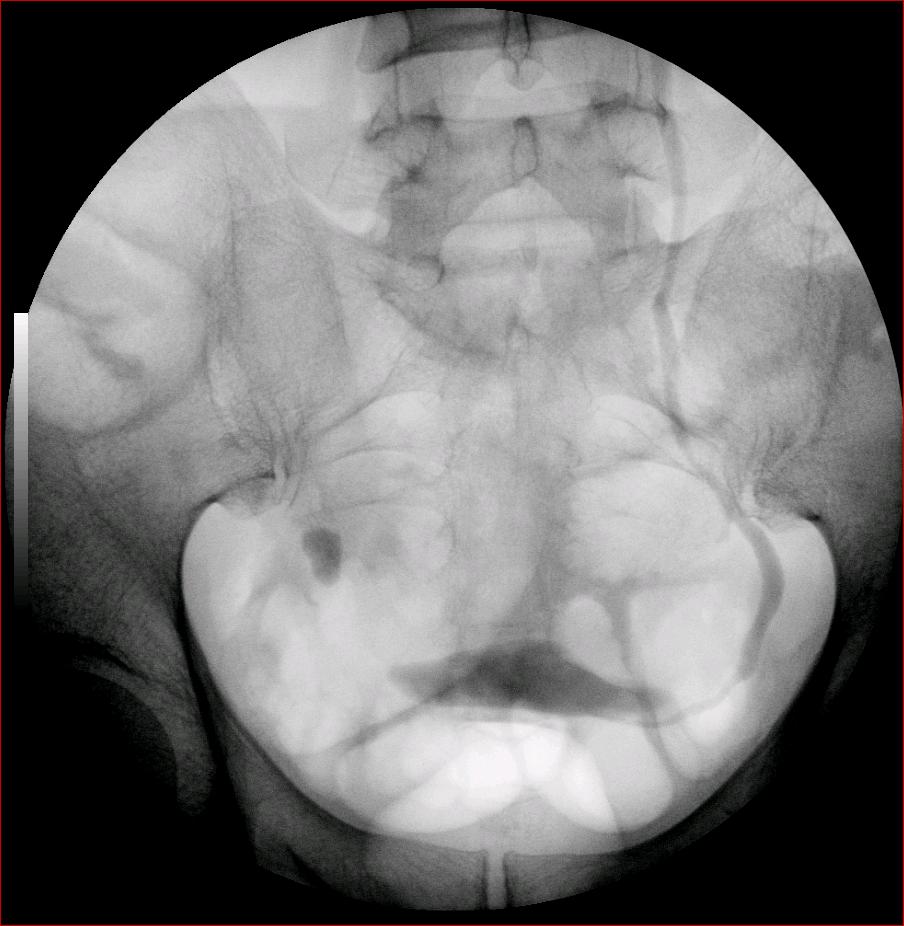

以下是引用luoxinjun在2008-2-18 15:54:00的发言:[br]右肾积水,右输尿管下端结石

以下是引用zhangxiangjun在2008-2-18 21:01:00的发言:[br]右输尿管盆段末端结石,继发其近端输尿管、右肾积水。

以下是引用hexue在2008-2-18 17:33:00的发言:[br]右输尿管下段结石并右肾及右输尿管积水扩张

以下是引用杀毒软件在2008-2-18 16:24:00的发言:[br]右输尿管下段结石,肾盂积水。